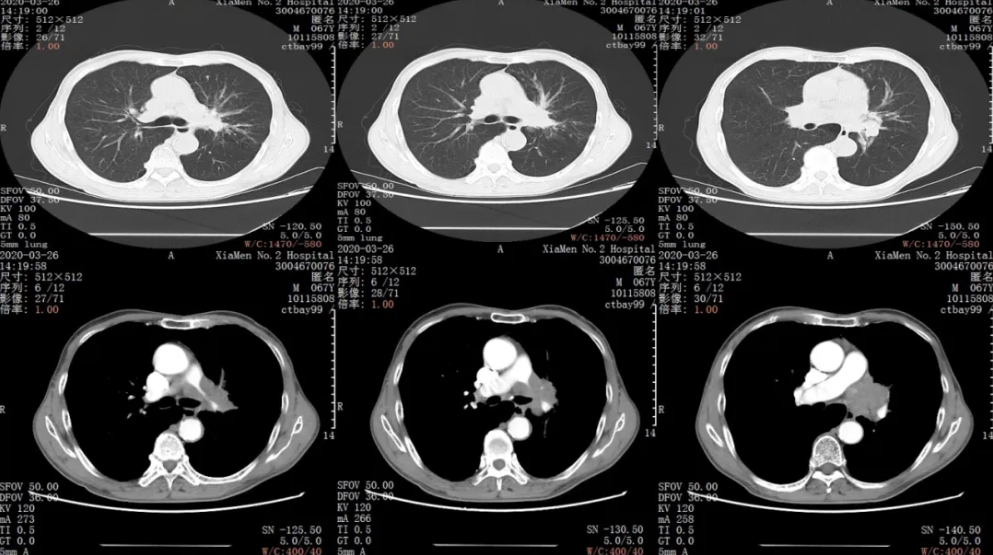

胸部CT平扫+增强:左肺门肿块侵犯左肺动脉,考虑中央型肺癌并阻塞性炎症,左肺肿瘤支气管播散不除外,纵隔及左肺门淋巴结转移可能,肺气肿

胸部CT平扫+增强:

疗效评价:PR (左肺门病症明显缩小,结构清晰)

后续治疗:2020-06-22日开始给予左肺门进行放射治疗

疗效评价:PR/SD(放疗结束后复查CT未见明显放射性肺炎及不良反应)

后续治疗:放射治疗结束后,继续给予原方案化疗2周期,复查胸部CT,疗效评价PR,病情稳定